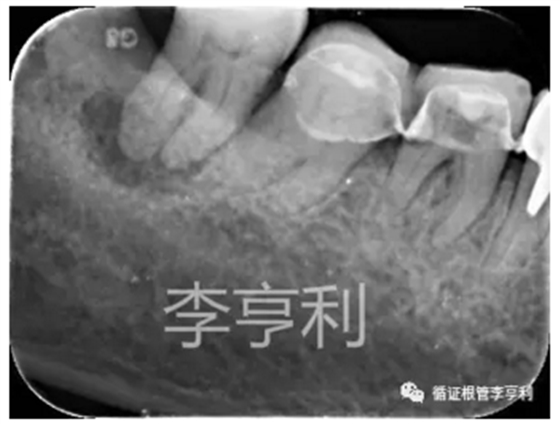

【轉診原因】:46器械分離

【病史】:46活髓牙,行冠修復后逐漸出現(xiàn)冷熱刺激痛及自發(fā)痛,轉診醫(yī)生診斷該牙為不可逆性牙髓炎,并開始根管治療。在疏通MB根的途中,發(fā)現(xiàn)#15 K 銼分離致根管無法疏通,隨后轉至我處

【輔助檢查】:遠中角度投射根尖片,見斷械影像移向近中,故判斷器械分離于近中頰根,根尖周未見明顯異常 (詳見CBCT┃如何使用傳統(tǒng)根尖片)